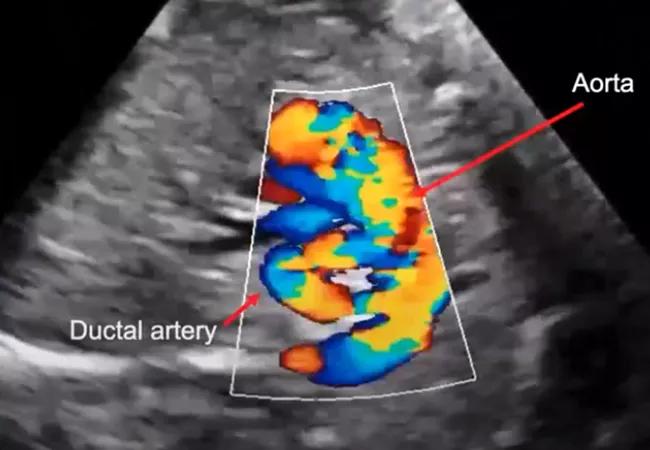

However, echo-informed planned management is far different in a case of ToF with pulmonary atresia, or “blue tet,” in which there is no visible anterograde flow from the right ventricle. This condition is much more severe, with no valve outlet or blood flow to the lungs. This baby must be delivered at the main campus and started on prostaglandin right away to keep the ductus arteriosus open until surgery, usually within a week to 10 days after birth.

Here, the use of fetal echo makes a major difference. “If we know about it and plan for it appropriately, we prevent a potential emergency,” Dr. Rao notes.